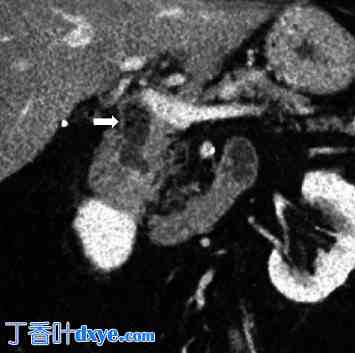

计算机断层扫描 (CT) 扫描显示一个 1.6 厘米的充满空气和液体的积聚物,最初被解释为十二指肠憩室。经检查,这被认为是远端 CBD 的胰腺内部分(图 1)。

图 1。

腹部 CT 扫描,箭头指示扩张的胰腺内 CBD,其中积聚了碎片和结石,类似于十二指肠憩室。